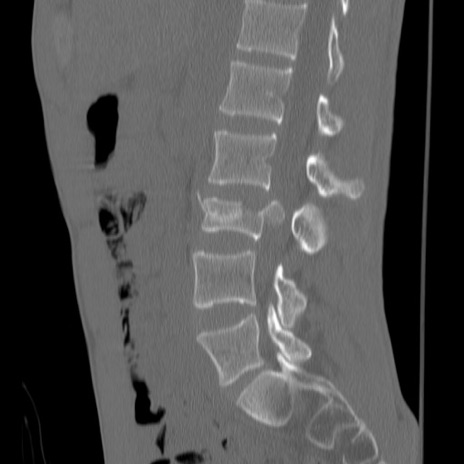

症例3 腰椎CT(矢状断像)

【症例】30歳代男性

【主訴】腰痛

【現病歴】本日旅行先で観光中に、友人と衝突し転倒し受傷。

【身体所見】麻痺なし、右下腿内側前面外側、左下腿内側に知覚鈍麻・しびれ

異常所見と診断は?

腰椎CT